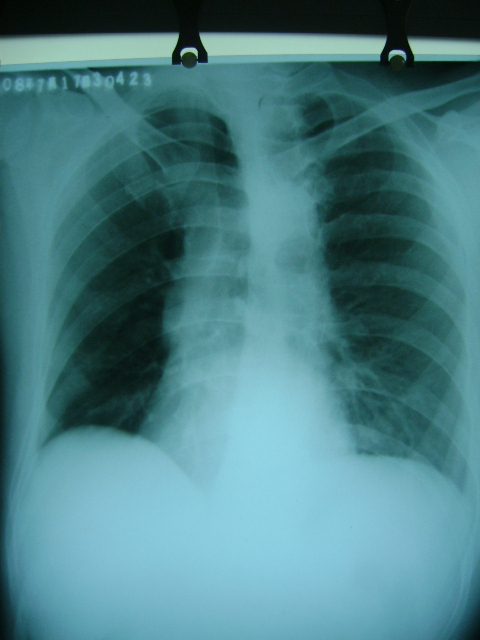

标题: X4564:右位心可能吗

m47y外伤发现

脊柱侧玩畸形,同事怀疑,本人不支持

看起不像哦,脊柱侧弯畸形重叠引起,主动脉弓影在左侧。

胸片类似斜位,心影右旋,应该可否定右位心吧。

轻度左前斜位造成的假象。

不可能为右位心,脊柱侧弯,胸廓畸形所致.

胸廓不对称,脊柱侧弯,导致心脏位置改变,请注意主动脉结,心尖位置,肯定不是右位心.